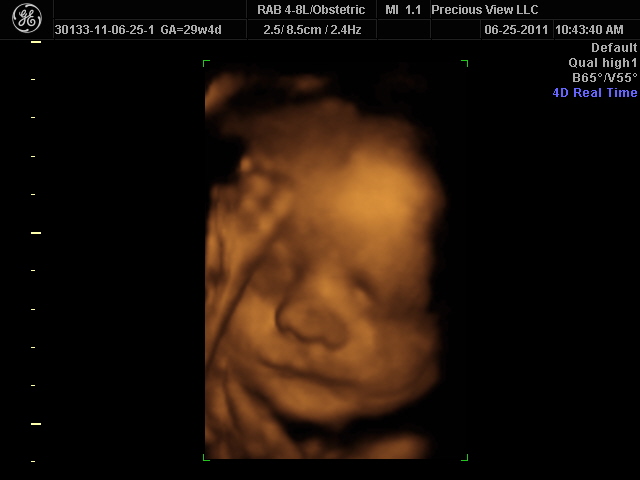

Baby at 29 weeks